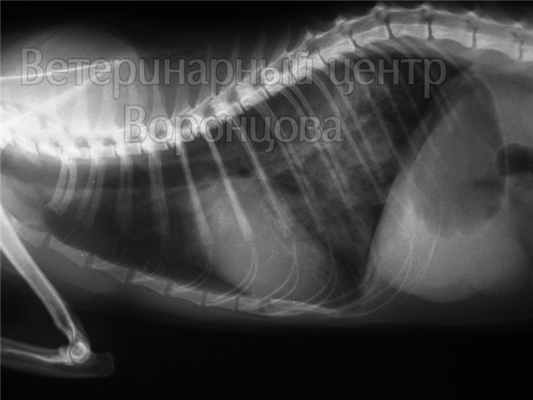

Золотым стандартом диагностики отека легких является рентгенография грудной полости в двух взаимно перпендикулярных проекциях. На рентгеновском снимке выявляют понижение прозрачности легочной ткани, расширение и «размытость» корней легких. Эти изменения могут быть как диффузными и затрагивать все доли легких, так и очаговыми, что встречается реже.

Отек легких на рентгене у животных